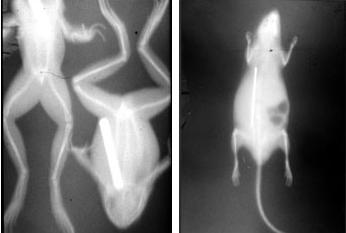

omedelbart omskriven i dagstidningar över hela världen. I Sverige skrev flera dagstidningar, bland andra Svenska Dagbladet, om den stora nyheten den 10 januari, endast 14 dagar efter det att Röntgen lämnade in sitt manuskript, som då ännu inte publicerats! Bild 3. I Sverige togs de första röntgenbilderna av fysiker på olika platser, de allra första av laborator Hjalmar Öhrwall i Uppsala i februari 1896 på metallföremål, döda grodor, möss och fiskar. Det mest intressanta var nog professor Fritiof Holmgrens hand där exponeringen tog en timme. Thor Stenbeck tog ungefär samtidigt röntgenbilder av ett träetui med kirurgiska instrument.

I november 1895 upptäckte Wilhelm Röntgen röntgenstrålarna och publicerade en av de första röntgenbilderna föreställande sin kollega von Köllikers hand (Bild 1). Den nya upptäckten spred sig snabbt till Sverige och redan i februari 1896 tog i Uppsala en bild på två grodor och en råtta samt av professor Fritiof Holmgrens hand (Bild 2). Exponeringstiden var en timme och istället för film användes glasplåtar.